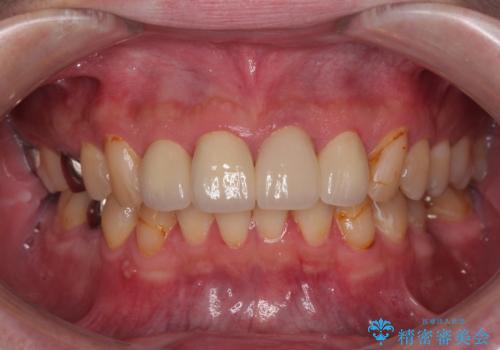

審美面、機能面共に大変満足していただきました。今後は左下の欠損部にインプラント治療を行っていく予定です。